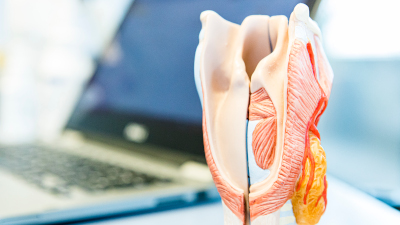

Tumore im Kopf-Hals-Bereich

Tumor im Bereich der Zunge, der Mandeln, des Mundes, des Rachens und des Kehlkopfes sowie der Speicheldrüsen und Lymphknoten.